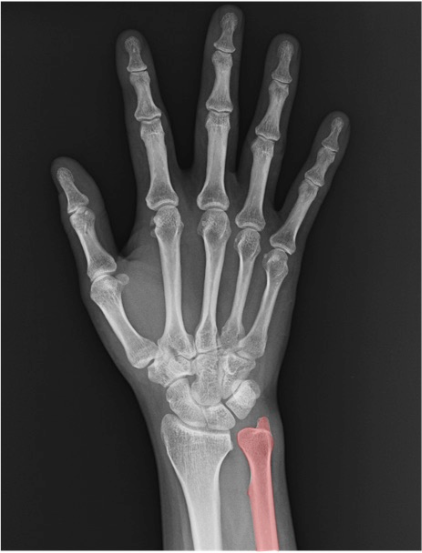

一目でわかる手根骨の解剖

手根骨、橈骨・尺骨、関節の解剖名とレントゲン画像所見

尺骨(ulna)

前腕の尺側骨。手関節X線では遠位部のみ視認。PAで橈尺関節(DRUJ)の整合、側面で重なり具合や背側/掌側転位の示唆を確認。

橈骨領域

橈骨(radius)

前腕の橈側骨。手関節X線では遠位橈骨(distal radius)が主要評価部位です。PA像では舟状骨窩(scaphoid fossa)と月状骨窩(lunate fossa)の連続性、DRUJ(遠位橈尺関節)の整合を確認。側面像では掌側傾斜(volar tilt)や背側転位、関節面段差(step-off)の有無をチェックします。